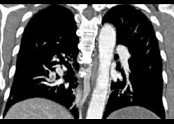

- 单项选择题男,56岁, 食管癌术后,胸痛, 呼吸困难,结合CT图像, 最可能的诊断是 ( )

B、肺栓塞